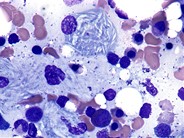

Category: Myeloid Disorders > Lysosomal storage disorders > Gaucher

Gaucher cells and Megacaryocytes can be seen in the bone marrow aspiration of a patient suffering from Gaucher disease.